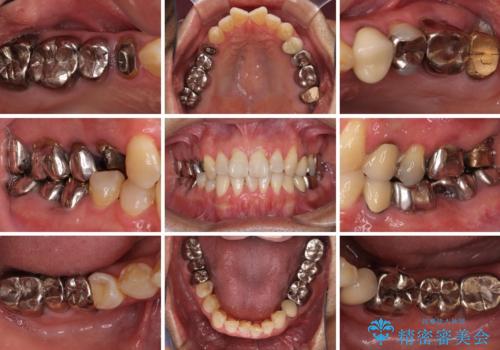

- 奥歯に違和感を感じており、抜歯の必要性を感じて来院された患者様です。

診査の結果、5本の奥歯を抜歯してインプラントによる補綴治療が必要と診断されました。

患者様が違和感を感じていない左下の奥歯の治療は今回は見送り、それ以外の治療が必要な奥歯を治療することとしました。

左上の奥歯は2本抜歯が必要であったため、治療期間中は右側に負担がかかり、頻繁に仮歯が壊れてしまいました。